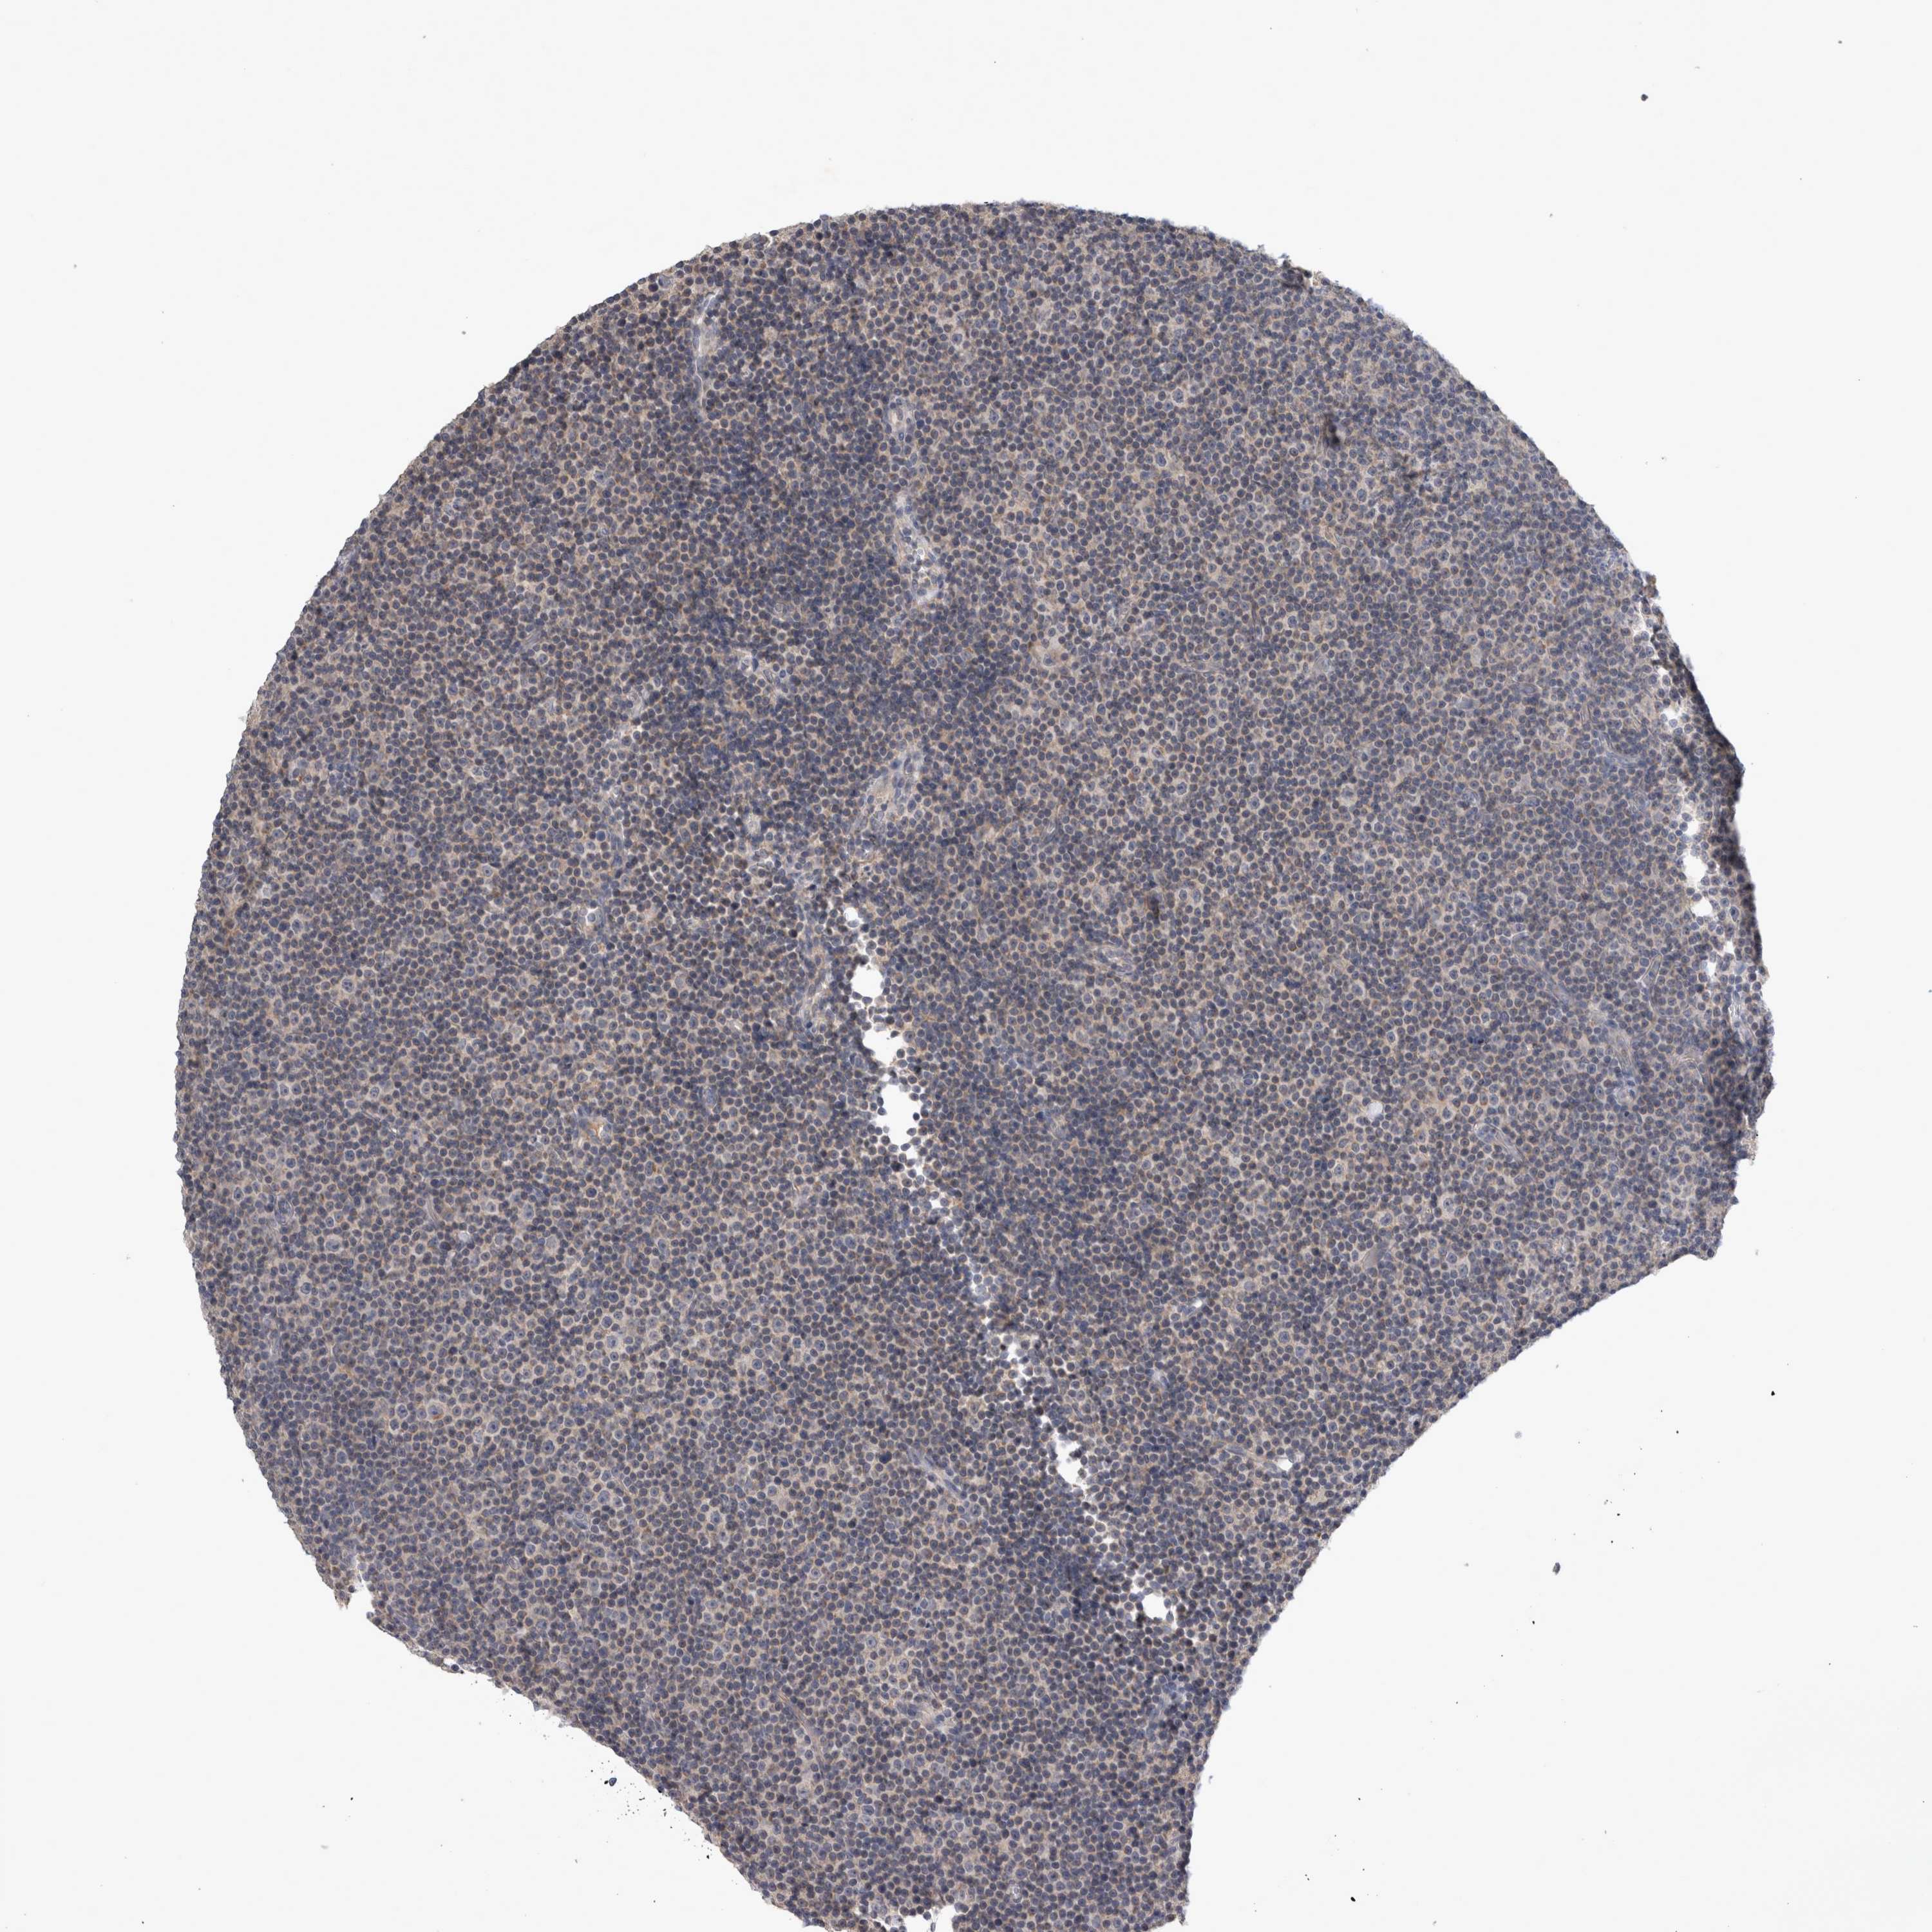

CANCER LYMPHOMA Show tissue menu

LYMPHOMA - Protein expressioni

A mouse-over function shows sample information and annotation data. Click on an image to view it in a full screen mode. Samples can be filtered based on level of antibody staining by selecting one or several of the following categories: high, medium, low and not detected. The assay and annotation is described here.

Each image is clickable and will lead to virtual microscopy that enables deeper exploration of all samples and also displays staining intensity scores, fraction scores and subcellular localization as well as patient and tissue information for each sample.

Antibody HPA026076

Staining

High

Medium

Low

Not detected

Intensity

Strong

Moderate

Weak

Negative

Quantity

>75%

75%-25%

<25%

None

Location

Nuclear

Cytoplasmic/membranous

Cytoplasmic/membranous,nuclear

Hodgkin's disease, NOS

Malignant lymphoma, non-Hodgkin's type, High grade

Malignant lymphoma, non-Hodgkin's type, Low grade